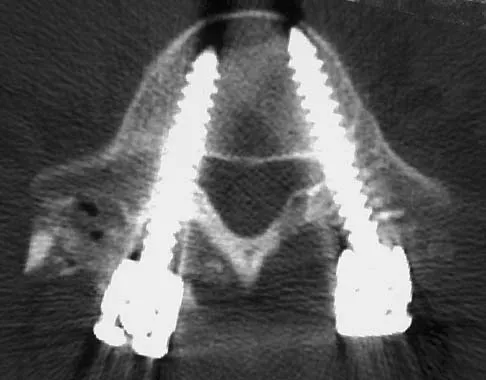

A 35-year-old male laborer with isolated posttraumatic degenerative arthritis of the right hip undergoes the procedure shown in Figure 8. What is the most appropriate position of the right lower extremity?

The primary indication for hip arthrodesis is isolated unilateral hip disease in a young, active patient. Avoiding abductor damage and preserving proximal femoral anatomy are imperative to allow conversion to a future total hip arthroplasty. Optimal positioning is 30 degrees of flexion to allow swing-through. Neutral abduction and adduction and slight external rotation allow the most efficient gait while allowing sufficient support in stance. A small degree of adduction is acceptable for a successful hip arthrodesis. Callaghan JJ, Brand RA, Pedersen DR: Hip arthrodesis: A long term follow-up. J Bone Joint Surg Am 1985;67:1328-1335.